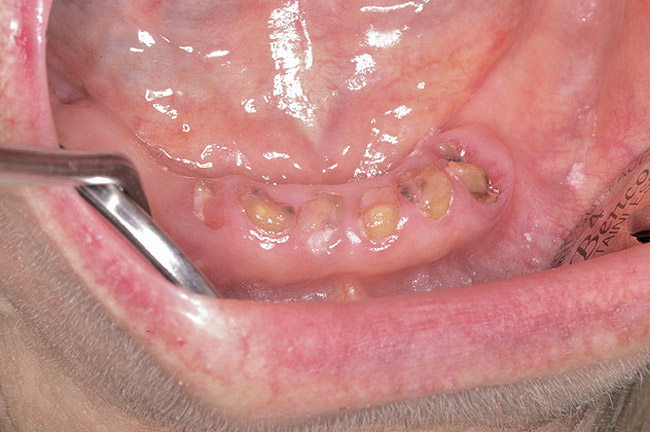

For patients on IV bisphosphonates, after bone is exposed, it is almost impossible to cover.15 Most cases worsen if surgical intervention is performed. Most patients must simply deal with the exposed bone and keep it clean so that bacterial infection does not occur. Figure 2 and Figure 3 show a postmetastatic prostate cancer patient with exposed bone. The treatment plan for this patient was to make a soft-lined denture that would not put pressure on the exposed bone and to check for bacterial infection on a routine basis. When dealing with patients on or about to begin IV bisphosphonate therapy, dentists need to be very astute. As stated earlier, this form of the drug has a much higher incidence of complications. These patients are often very sick and immuno-compromised and, therefore, must be managed properly. Pre-IV bisphosphonate patients (ie, those not yet receiving the drug) are much easier to manage than patients already receiving the drug. First, ask the treating physician, usually an oncologist, if he or she can wait 2 months before the drug is given. If the cancer is severe, it may not be possible to wait. Dental healthcare provides should make use of whatever time can be made available before bisphosphonate treatment begins.16 This time should be used to get a full-mouth series of radiographs and to remove all dental infections, including all decay. If decay cannot be removed completely, the tooth should be considered for extraction. Before IV therapy begins, patients are at a lower risk for extraction complications than they are during bisphosphonate therapy.

Figure 2  Postmetastatic cancer patient with BRONJ (A) in the lower right quadrant and (B) in the lower left quadrant.

Figure 2

Figure 3  Postmetastatic cancer patient with BRONJ (A) in the lower right quadrant and (B) in the lower left quadrant.

Figure 3